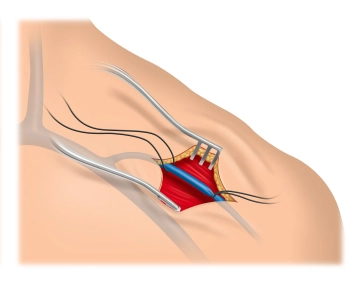

Tras la desinfección cutánea y la cobertura estéril, se realiza la anestesia local a lo largo del surco deltopectoral izquierdo, así como en la zona del bolsillo del generador. Incisión cutánea de aprox. 6-7 cm de longitud sobre el surco y sección de la subcutis mediante un bisturí eléctrico. Tras la colocación de un separador de herida y una hemostasia sutil con coagulación bipolar, se procede a la preparación del bolsillo del generador.

1. La preparación del bolsillo del generador debe realizarse de forma roma, es decir, digital, para evitar hemorragias.

2. Se recomienda la posición del bolsillo sobre el centro del M. pectoralis major, donde raramente se observa una dislocación posterior del generador hacia la axila.

3. En la mayoría de los casos, los generadores de DAI se posicionan submuscularmente debido a su tamaño –a diferencia de los generadores de marcapasos–. Incluso en casos de subcutis escasa (niños, pacientes con bajo peso), no se aconseja la colocación premuscular debido al riesgo de necrosis por presión de la piel («decúbito interno»).